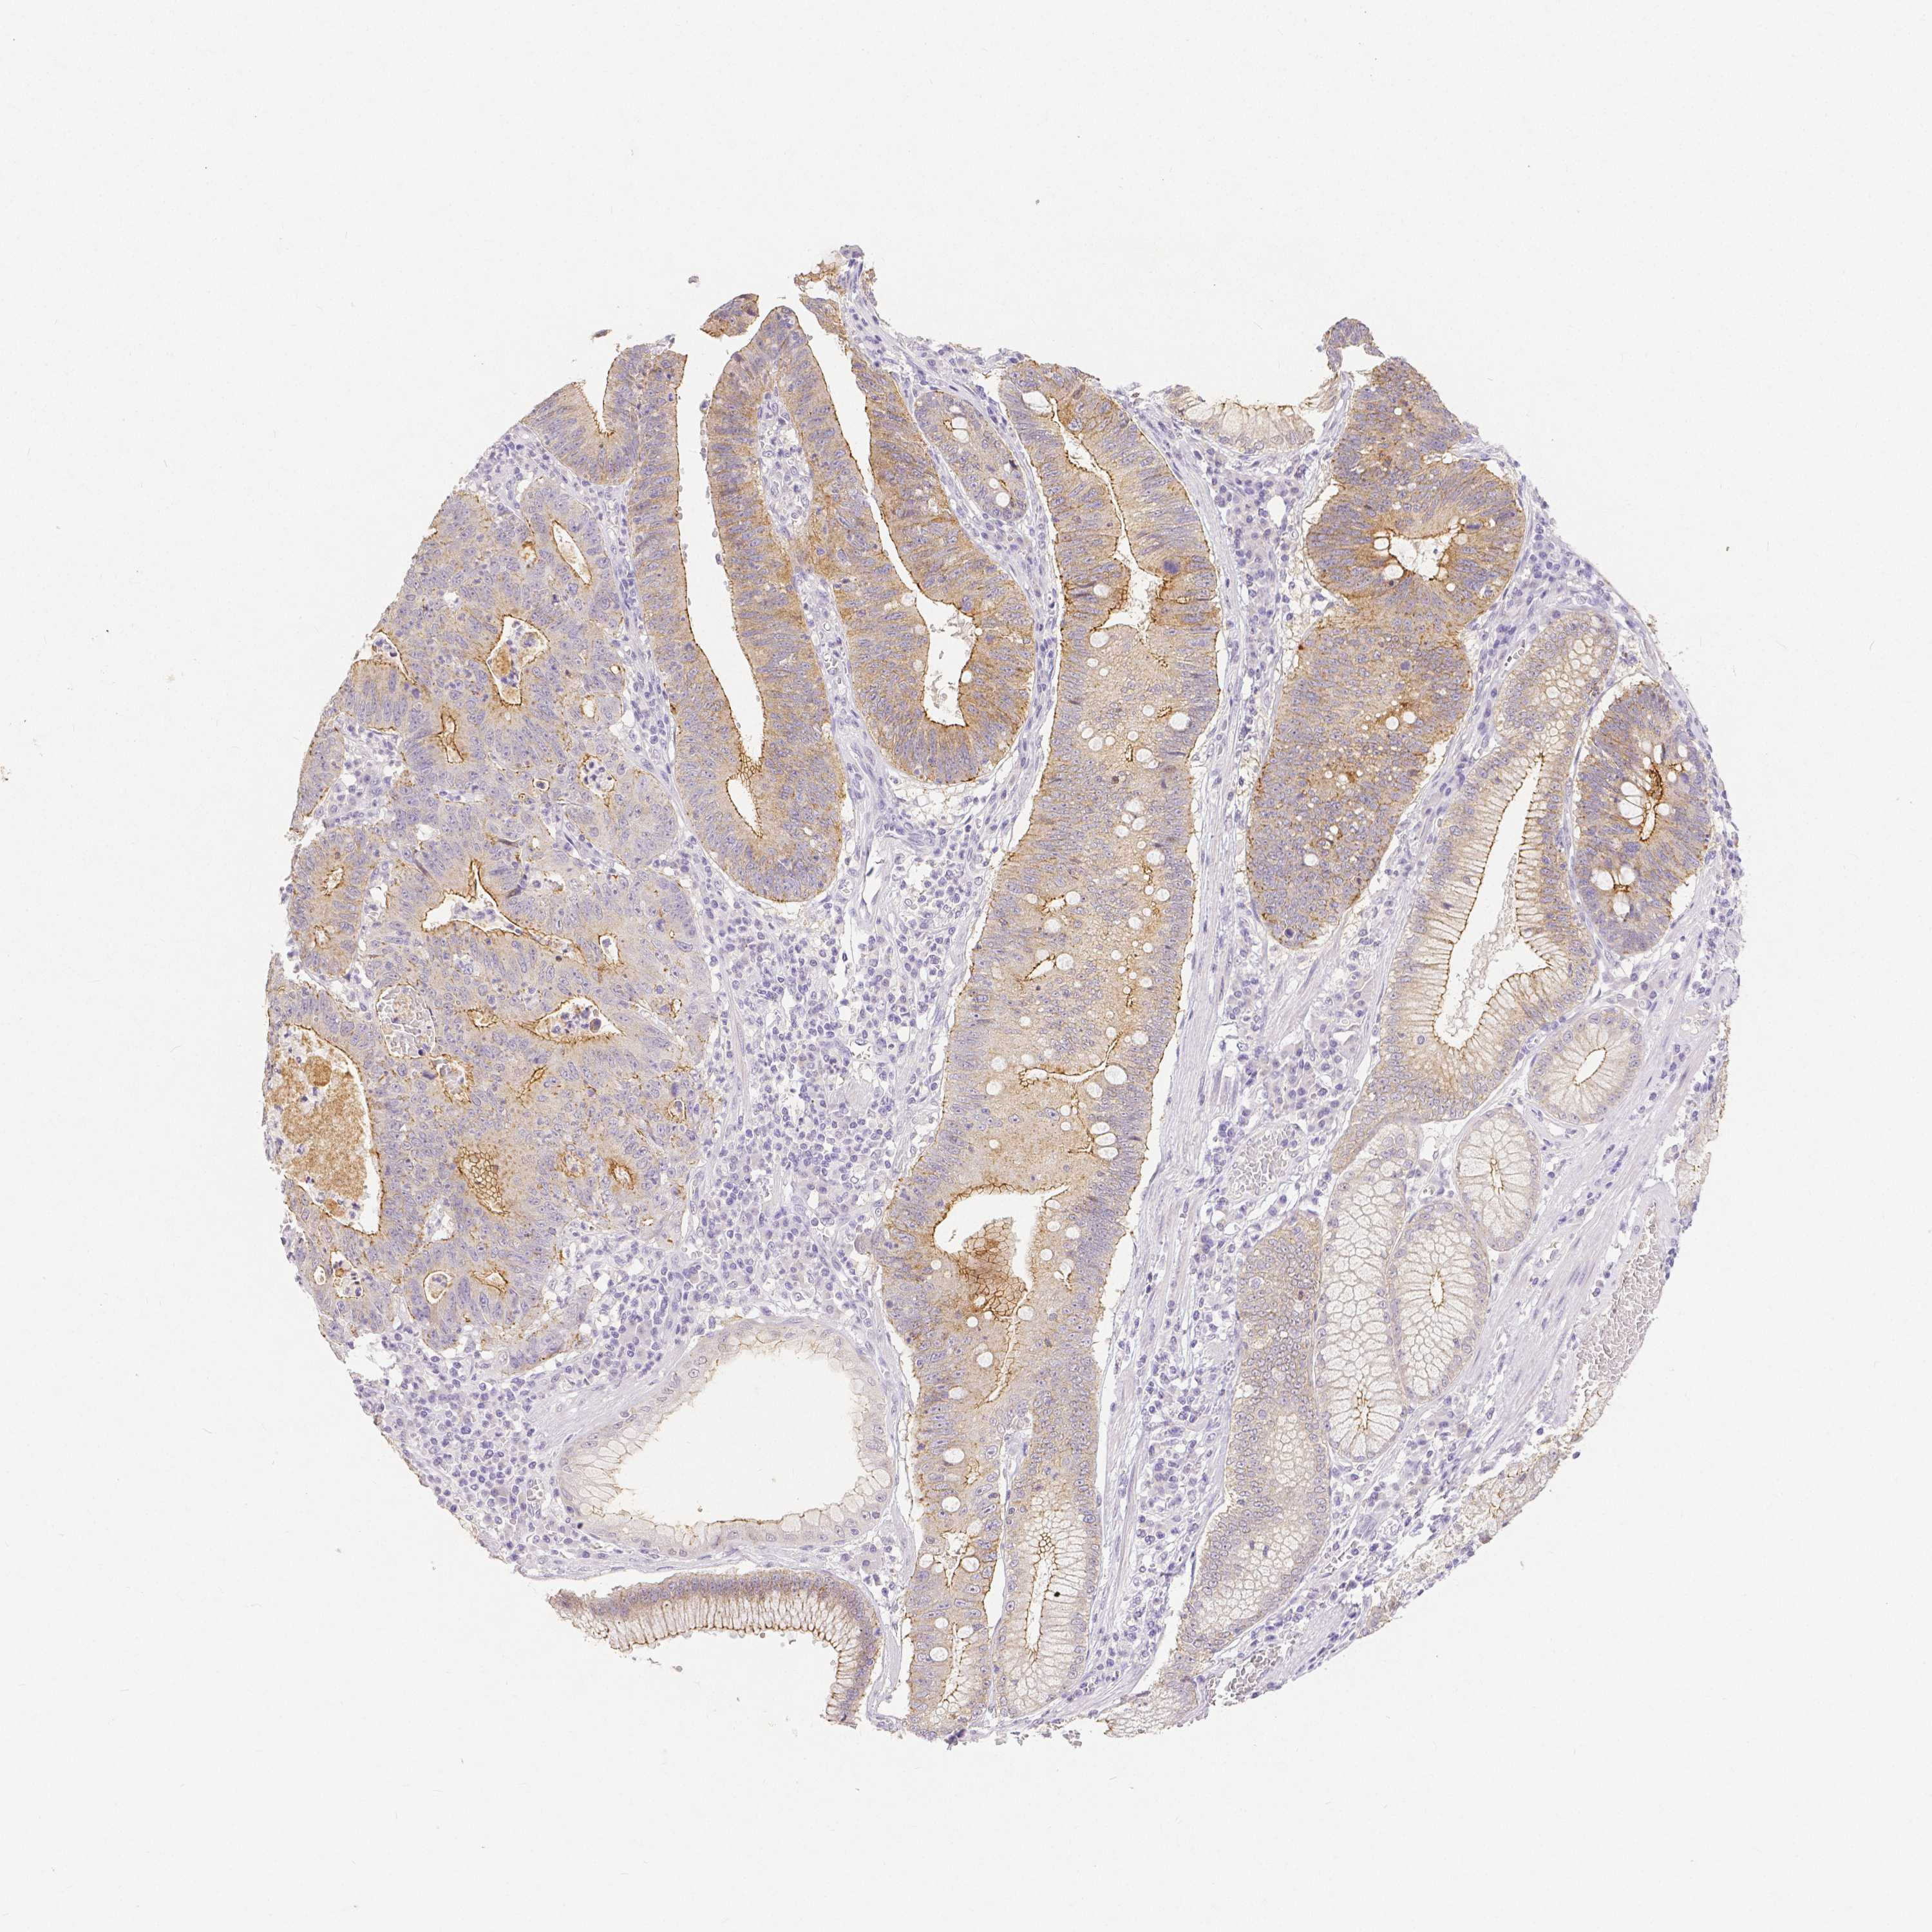

STOMACH CANCER - Protein expressioni

A mouse-over function shows sample information and annotation data. Click on an image to view it in a full screen mode. Samples can be filtered based on level of antibody staining by selecting one or several of the following categories: high, medium, low and not detected. The assay and annotation is described here.

Antibody stainingi

Antibody staining in the annotated cell types in the current human tissue is reported as not detected, low, medium, or high, based on conventional immunohistochemistry profiling in selected tissues. This score is based on the combination of the staining intensity and fraction of stained cells.

Each image is clickable and will lead to virtual microscopy that enables deeper exploration of all samples and also displays staining intensity scores, fraction scores and subcellular localization as well as patient and tissue information for each sample.

HPA005933

CAB013075

CAB068212

CAB068213

CAB068214

Staining

High

Medium

Low

Not detected

Intensity

Strong

Moderate

Weak

Negative

Quantity

>75%

75%-25%

<25%

None

Location

Nuclear

Cytoplasmic/membranous

Cytoplasmic/membranous,nuclear

Adenocarcinoma, NOS

Adenocarcinoma, High grade